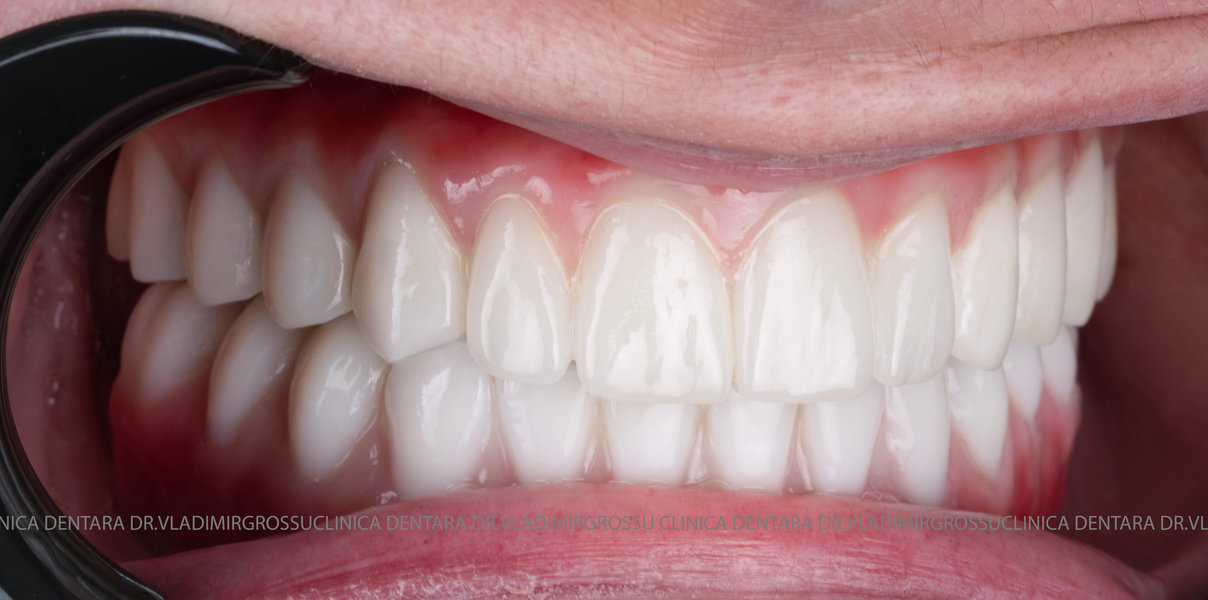

La aproximativ 6 luni de la prima etapă, pacientul revine pentru protezarea definitivă. În această fază, medicul lucrează la nivelul multiunit-urilor și nu direct pe implanturi, ceea ce reduce riscurile pentru implant în etapa protetică.

Pentru proteza definitivă:

- 4 abutment-uri permanente pe multiunit-uri;

- Proteză definitivă din metaloceramică sau zirconiu pe o structură metalică, cu 12 unități (soluția recomandată).

Pentru pacienții cu edentație extinsă sau dinți nefuncționali, conceptele All-on-4 și All-on-6 oferă soluții fixe, moderne și eficiente, care asigură estetică, confort și funcționalitate superioară față de proteza mobilă.